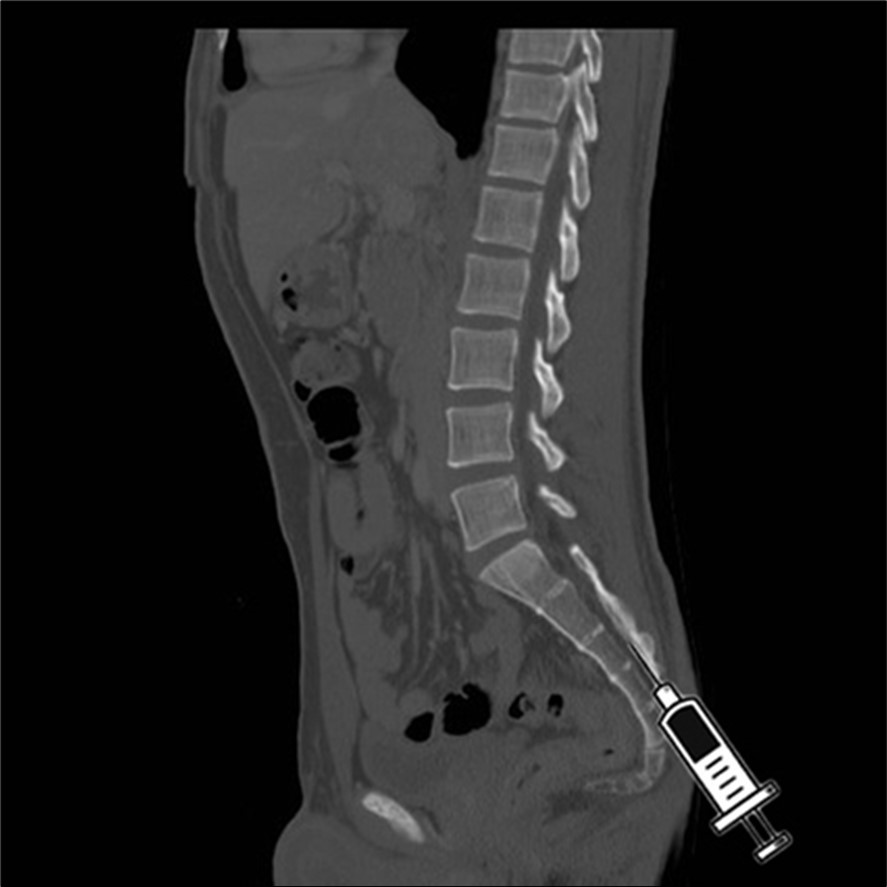

Sacral injections, also known as caudal epidural injections (Figure 2- Figure 3), can be an effective treatment option for some individuals with lower back pain. These injections involve injecting numbing medicine and a steroid into the epidural space near the tailbone to alleviate nerve pain and inflammation. While the effectiveness of sacral injections varies among patients, they are generally considered safe with minimal risks of complications.

Figure 2.oblique view of the injection in the hiatus.

Figure 3.sagittal C.T. scan view of the injection in the hiatus.